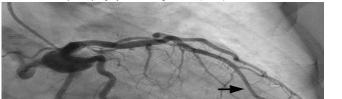

This leads me to the patient’s imaging, which is often key to reaching a final diagnosis in patients presenting with hemoptysis. As noted earlier, advanced imaging such as computed tomography (CT) is only possible once the patient has been sufficiently stabilized. Therefore, many physicians may have to initially rely on a portable chest radiograph (CXR) alone. A CXR is a bit of a mixed bag, with widely variable rates of diagnostic ability reported in the literature. Sometimes it can identify a localizing lung lesion such as a tumor or cavitation, or potentially a more diffuse process such as pneumonia or diffuse alveolar hemorrhage. This patient’s CXR fits more in the latter category with diffuse bilateral airspace disease and air bronchograms. It is fortunate that he was also able to receive a CT angiography (CTA), as this is often the ideal imaging study to identify the cause of bleeding in hemoptysis, especially if it is from a culprit lesion. As most cases of massive hemoptysis are from the bronchial arterial system, it is worth noting that this CTA should ideally be protocoled differently from the traditional pulmonary artery CTA used when evaluating for pulmonary embolism.1 This patient’s post-intubation CTA demonstrated widespread ground-glass opacities with prominent septal lines, dependent consolidation, and air bronchograms in the bilateral lung bases suggestive of diffuse alveolar hemorrhage and hemorrhagic pneumonia.

At this point, a cardiovascular etiology seems unlikely. The CTA did not identify any vascular malformations or culprit

lesions. The symptoms are too profound for mitral valve stenosis, and there was no significant coagulopathy within the patient’s labs. The CT imaging similarly appears to exclude malignancy and any traumatic injury, and there was no history to suggest the latter. This leaves me focused on pulmonary and infectious etiologies of this patient’s presentation.